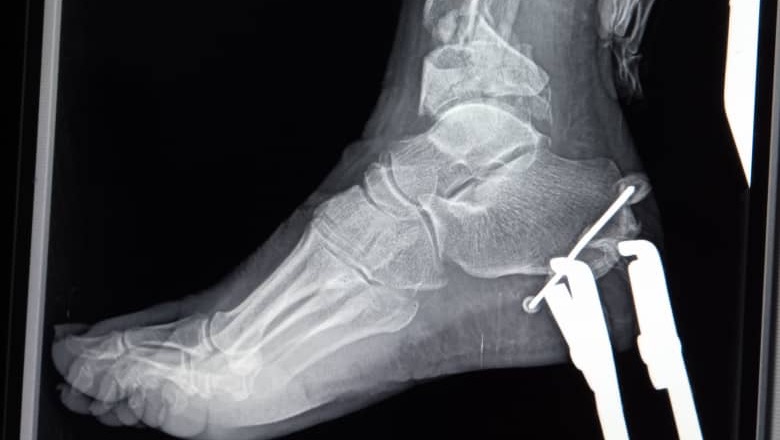

I am Xiomara Herrera and I am here to ask for help for my sister Alida Herrera who on August 24 suffered a car accident that caused her a multifragmentary pilon fracture of the right tibial Gustilo Anderson III B and a multifragmentary fracture of the right distal fibula. She urgently requires surgery consisting of cleaning and repair of the retinaculum and tendons of the right ankle, open reduction and percutaneous pinning with a special external Delta frame fixator, open reduction plus percutaneous pinning with Kirshner wires. The costs are inaccessible to our family, which is why we require the support and collaboration of family, friends and everyone who can join us in this cause in order to raise the amount of $10,000 needed to cover surgery, medical and subsequent expenses. Additionally, the rehabilitation therapies that allow Alida to walk again and recover her quality of life. We also ask you to join in prayers for the speedy recovery of my sister Alida. Thanks and blessings!